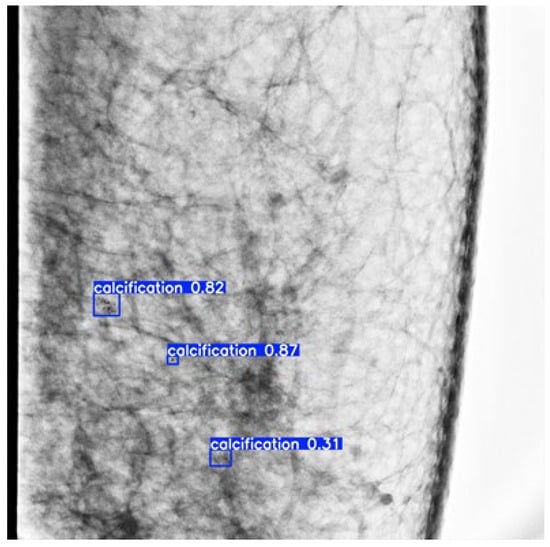

3.2. Visual Presentation of Microcalcification Detection Results

Several images were randomly selected from the dataset for inference tests using the trained weights. The results are shown in Figure 4. The blue box indicates the final convergence result of the generated prediction box. The blue background with white text indicates the category name (calcification) and its classification probability.

Figure 4.

Schematic diagram of microcalcification detection results of mammography.